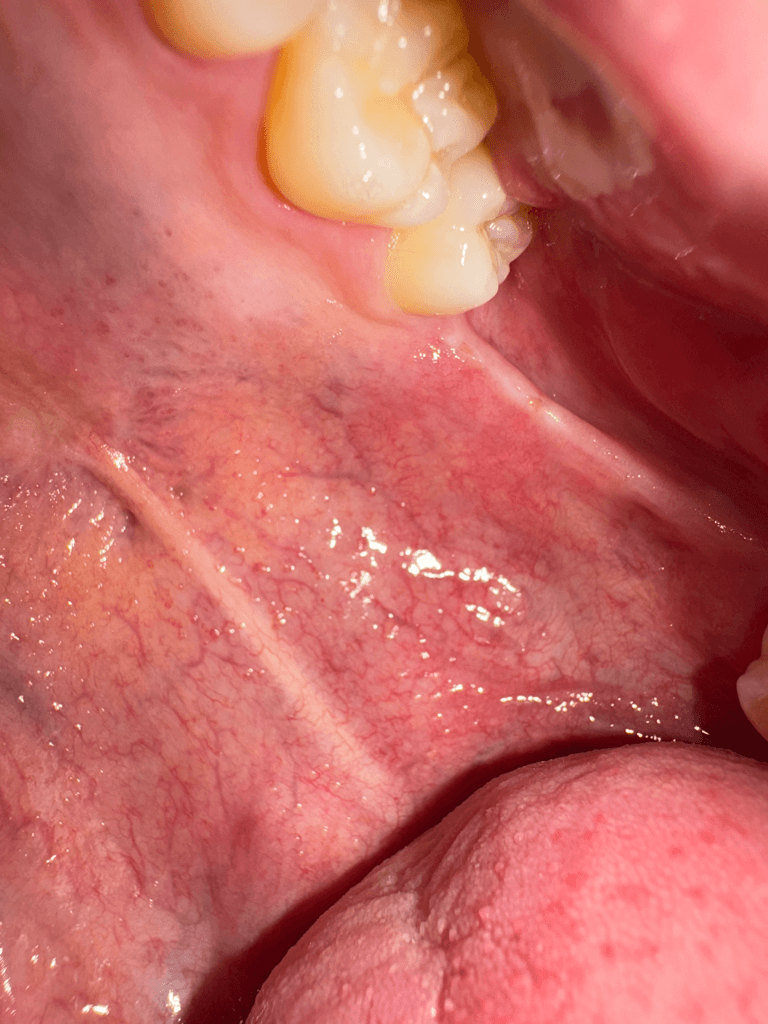

왼쪽 위아래 사랑니가 나야할 자리에 위아래로 연결된 끈 같은게 있는데 한 두달전부터 입벌릴때마다 땡기고 아픕니다. 오른쪽 아래어금니 크라운을 씌울 때 입을 계속 벌리고있었는데 그 때부터 의식하게돼서그런지 자꾸 신경쓰입니다. 사랑니가 나는 자리에도 약간 꺼끌꺼끌하게 상처같은게 나있는 것 같아요(혀로 만지면 느껴집니다.) 입을 최대한 크게 벌리면 저 끈같은게 끊어질 듯 아프고 사진도 자세히 보시면 말씀드린 끈같은것에 노란색 고른같은게 있어보입니다. 구강암같은 것일까요...? 치과에서는 별 말씀 없으셨었습니다.

1. 해당 구조는 pterygomandibular raphe라고 하며 정상 구조물입니다.

3. 노란색은 구강 내 지방조직 내지는 염증으로 추측됩니다.

저부위에 상처가 생겨서 그러는거 같으니 당분간은 입을 크게 벌리는건 조심하시고 그쪽부위에 자극이 가지 않도록 해주시는게 좋을것같습니다.